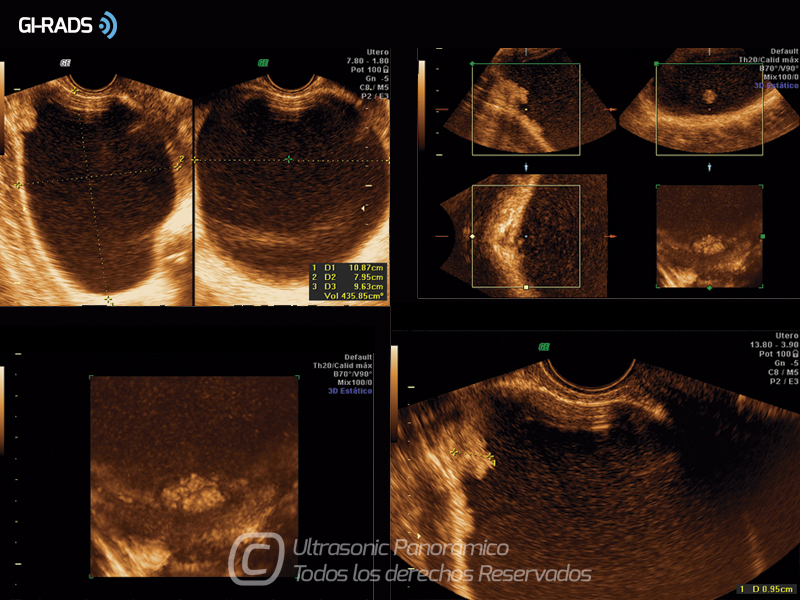

• Patologías Benignas – Cistoadenoma